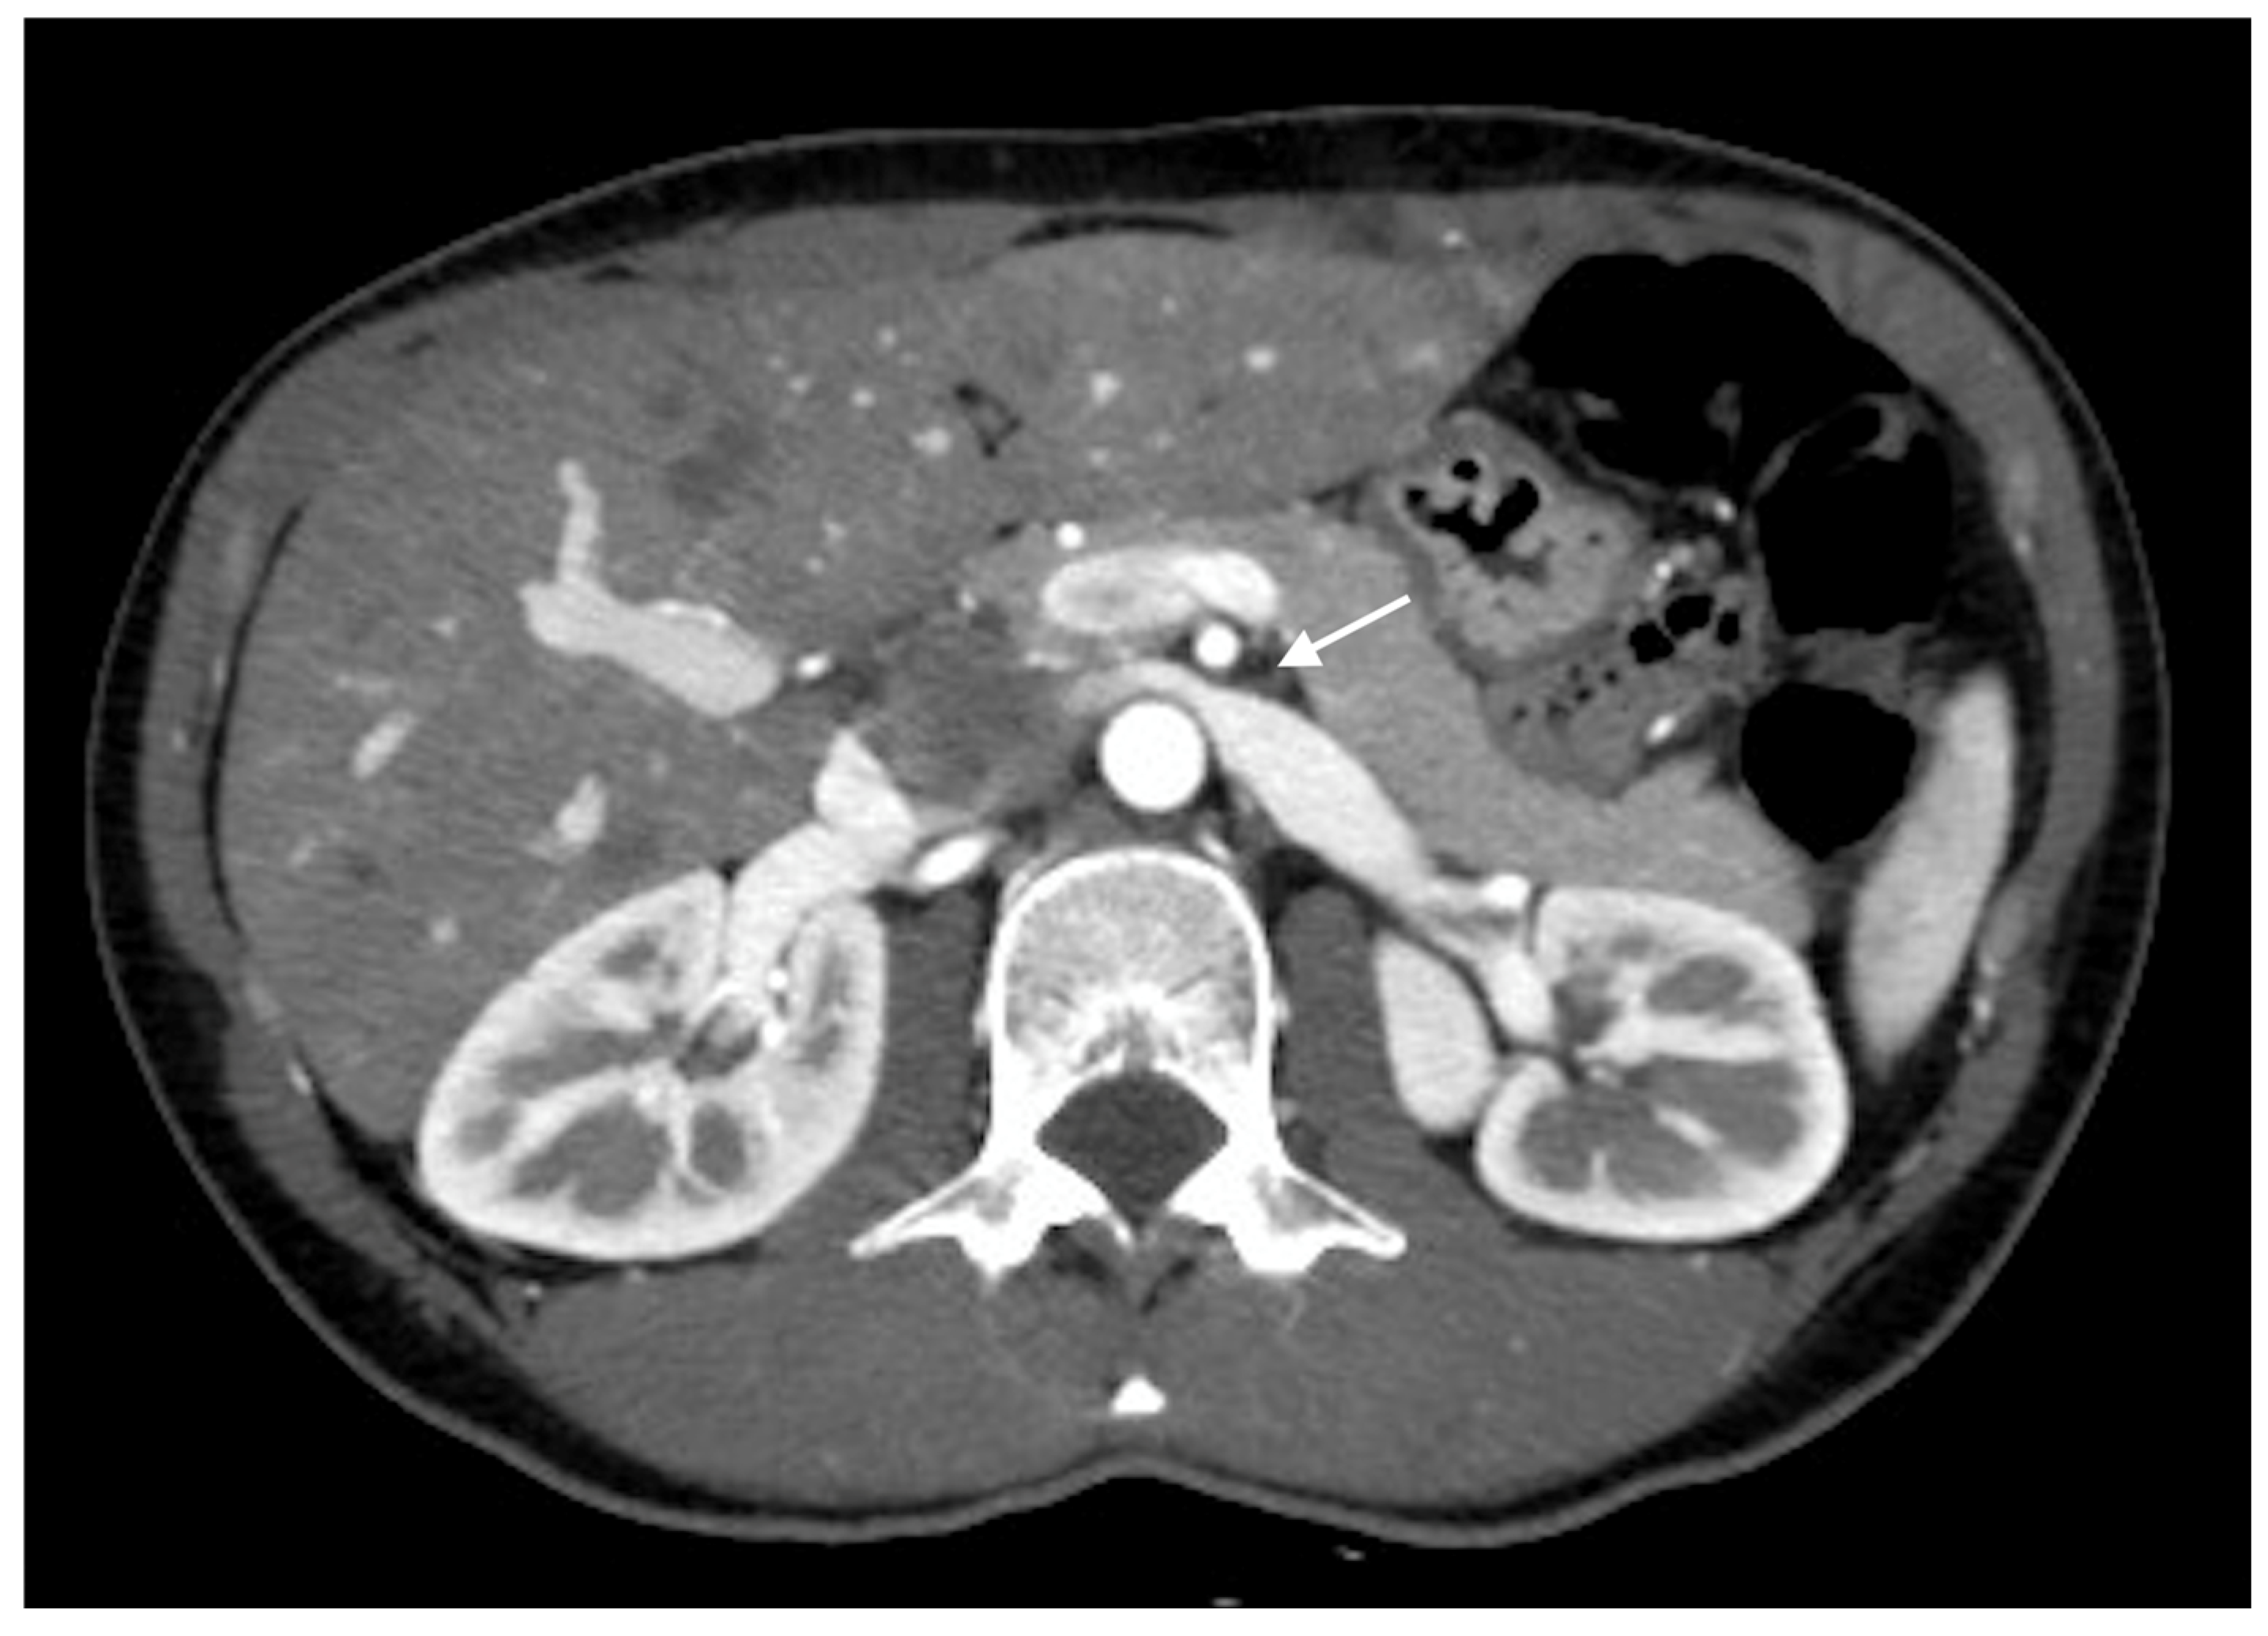

Nutcracker Syndrome as an Uncommon Cause of Isolated Hematuria in Adults

Case Presentation